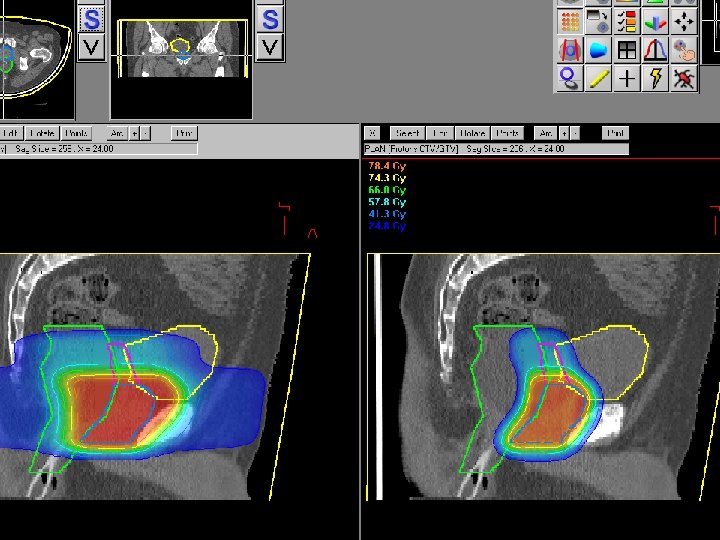

Dose vs. Depth for Protons In General, Effective Dose = RBE * Physical dose

Dose vs. Depth in patient for various Radiation Fields